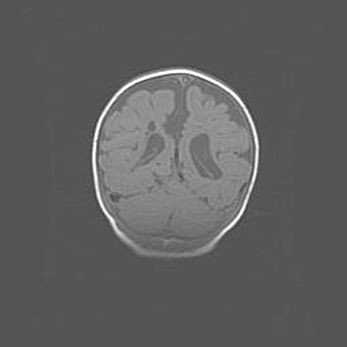

Сообщающаяся гидроцефалия. Кистозная энцефаломаляция головного мозга.

Возраст: 3 месяца 4 дня

Вес: 3100 г

Пол: женский

Окружность головы: 34 см

Срок гестации: 31 неделя

Кистозная энцефаломаляция головного мозга - одна из форм поражения головного мозга в детском возрасте. Характеризуется возникновением множественных и распространённых кист в коре, белом веществе и подкорковых образованиях головного мозга у плодов, новорождённых и детей раннего возраста. Развитие кистозной энцефаломаляции связано с внутриутробной асфиксией и гипотонией, родовой травмой, тромбозом синусов, пороками развития сосудов, инфекциями, сепсисом и другими причинами. Наиболее значимые инфекционные агенты: вирусы простого герпеса, цитомегалии, краснухи, токсоплазмы, энтеробактерии, золотистый стафилококк и другие.